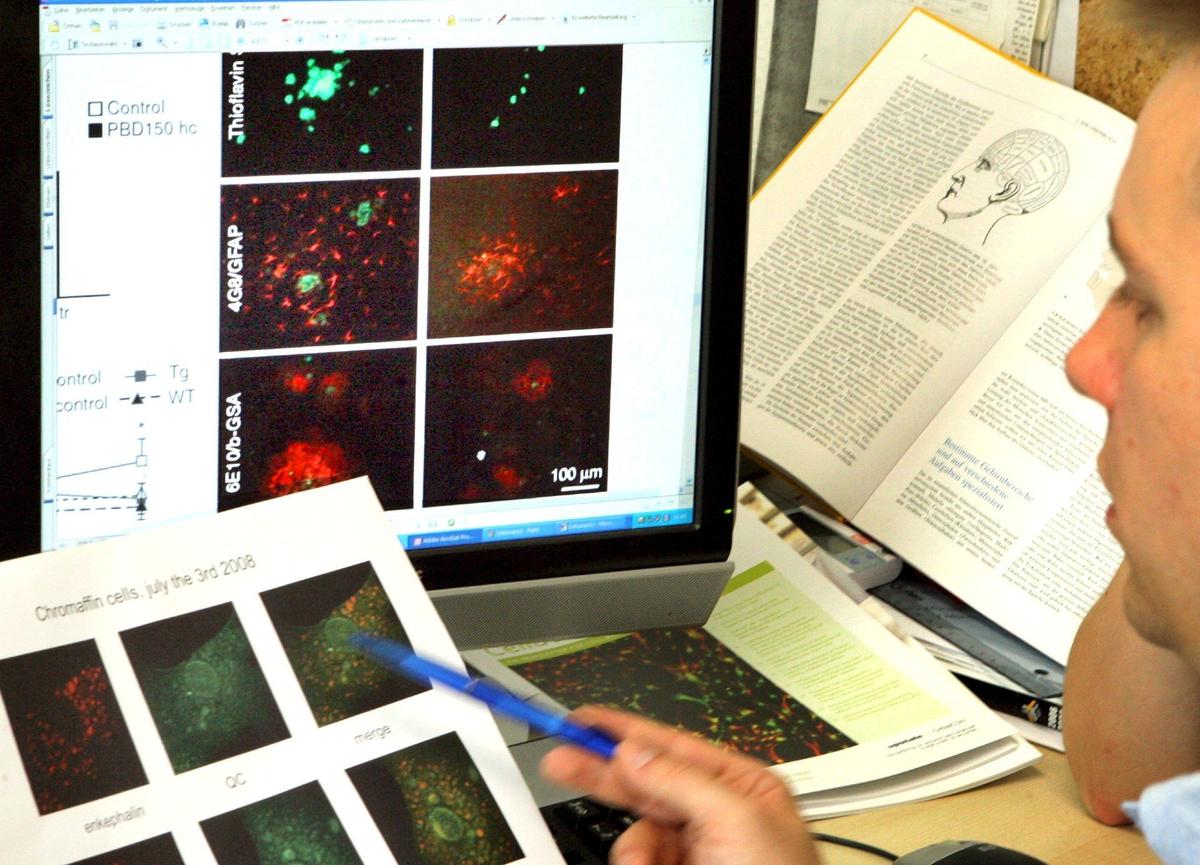

Теперь, наверное, можно как раз перейти к леканемабу. Сама молекула начала разрабатываться в начале двухтысячных годов, а затем она прошла несколько этапов клинических исследований. Самое резонансное из них — это как раз то, которое было опубликовано совсем недавно в авторитетном журнале New England Journal of Medicine. В рамках исследований препарат вводился в течение 18 месяцев, он также вводился внутривенно, как и адуканумаб. Как и адуканумаб, леканемаб относится к классу так называемых моноклональных антител. То есть это антитело, специально разработанное для того, чтобы, в случае этих двух лекарств, связываться с агрегатами бета-амилоида. Соответственно, один из общих подходов к разработке лекарственных препаратов от нейродегенеративных заболеваний в настоящее время — это разработка специализированных антител, призванных связываться с этими патологическими белками, которых не должно быть в норме. Связывание антитела с этим белком приводит к запуску иммунного механизма, когда при помощи клеток иммунной системы ненужный «плохой» белок утилизируется.

И тут мы переходим, собственно, к леканемабу, а именно к тому, что это тоже моноклональное антитело, которое направлено также против бета-амилоида. Надо отметить, что разрабатываются антитела и против тау-белка. Леканемаб отличается от адуканумаба тем, что он лучше всего связывается с протофибриллами бета-амилоида. Протофибриллы представляют собой «предзрелую» форму патологического бета-амилоида.

Еще интересный факт: в клинической разработке и адуканумаба, и леканемаба участвует одна и та же компания — «Biogen». В случае леканемаба, помимо Biogen, разработчиком выступает также компания «Eisai». Есть еще компания «Roche», которая занимается разработкой своего собственного моноклонального антитела против бета-амилоида — гантенерумаба, похожего по своему профилю в плане того, какие типы бета-амилоида оно связывает, на адуканумаб, но это уже другая история.

Леканумаб вводится также, как и адуканумаб, внутривенно. В сравнении с адуканумабом, согласно недавно опубликованным результатам клинического исследования Clarity AD, плюс в том, что на фоне лечения леканемабом были достигнуты не только суррогатные конечные точки, но и твердые конечные точки. Вот это глобальное принципиальное отличие.

Несмотря на то, что есть очень много данных в пользу этой теории, данные огромного числа клинических исследований, которые используют такой подход, — все пока либо полностью отрицательные, либо такие же неоднозначные, как с адуканумабом и с леканемабом. Например, в случае так называемых синуклеинопатий — болезни Паркинсона и мультисистемной атрофии — тоже изучаются подходы к иммунотерапии: как пассивная иммунизация моноклональными антителами, так и активная иммунизация, когда при помощи специальной вакцины иммунную систему заставляют вырабатывать иммунный ответ по элиминации альфа-синуклеина. Но и там тоже применение этих подходов либо полностью провалилось, либо результаты очень неоднозначны, так скажем.

А тут еще ложку дегтя добавила вот эта тоже резонансная публикация в журнале Science в этом году: о том, что, возможно, в одной из высокоцитируемых публикаций в журнале Nature о болезни Альцгеймера, опубликованной в начале 2000-х годов, вообще были сфальсифицированные изображения. Это не подрывает полностью концепцию бета-амилоида как важной структуры патогенеза в болезни Альцгеймера, но тем не менее, это было одно из исследований, на котором в дальнейшем базировался ход изучения патогенеза, то есть механизмов развития болезни Альцгеймера.